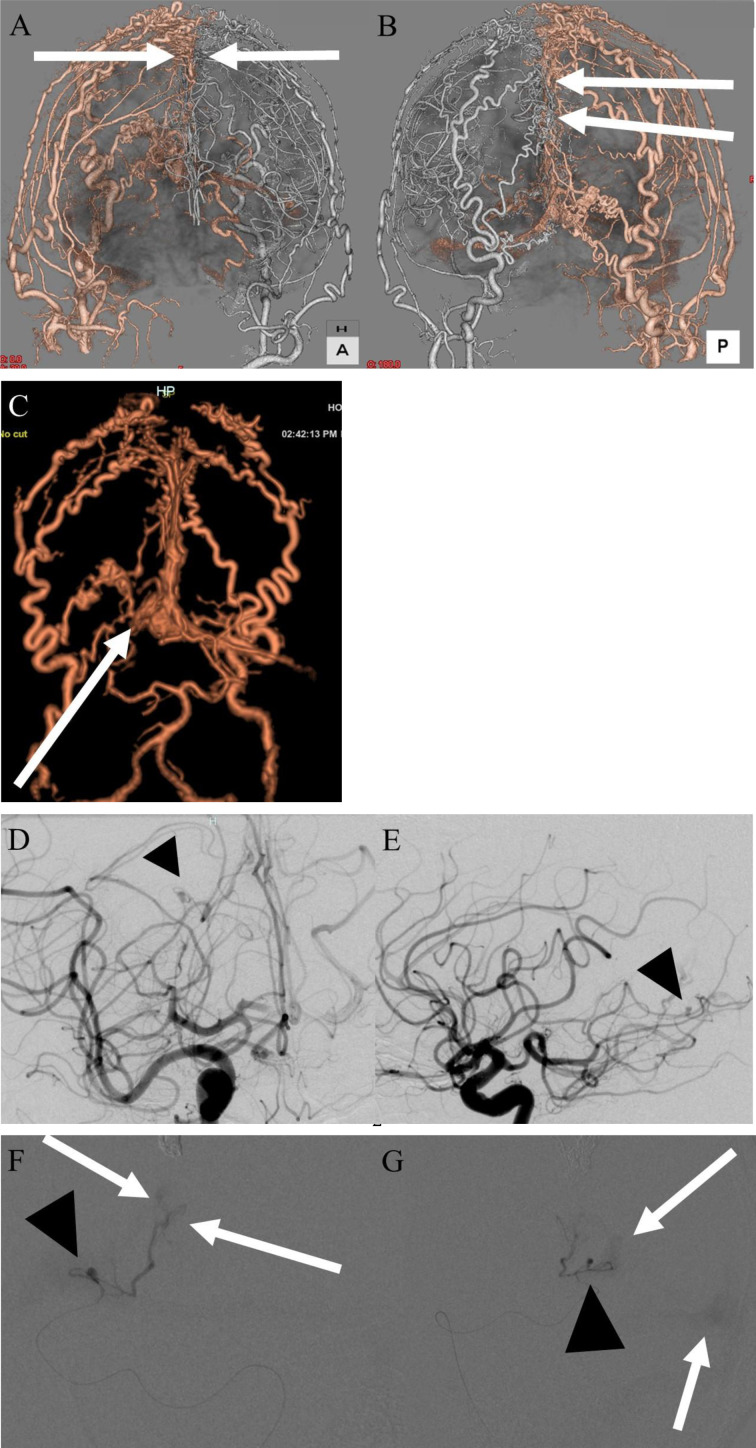

Objective: This report describes a rare case of a dural arteriovenous fistula of the falcine sinus associated with a flow-related aneurysm.

Patient and methods: A 68-year-old man presented with severe headache secondary to an intracranial hemorrhage. The bleeding was caused by a dural arteriovenous fistula (dAVF) of the falcine sinus with a flow-related aneurysm of the dural branch of the right posterior cerebral artery.

Results: Trans arterial obliteration of the aneurysm and its feeder using glue and trans venous embolization of the draining portions using a coil were successfully performed.

Conclusion: The unusual coexistence of a flow-related aneurysm on the feeder of the dAVF resulted in a unique hemorrhage.